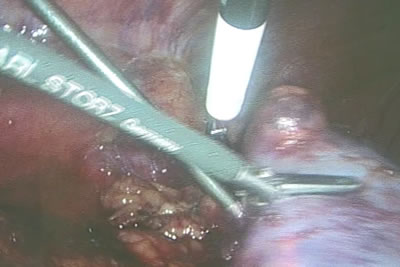

Специальным крючкообразным инструментом, на который подается

монополяный ток, намечаются границы будующей резекции.

Специальным крючкообразным инструментом, на который подается

монополяный ток, намечаются границы будующей резекции.

Специальным крючкообразным инструментом, на который подается

монополяный ток, намечаются границы будующей резекции.

Специальным крючкообразным инструментом, на который подается

монополяный ток, намечаются границы будующей резекции.